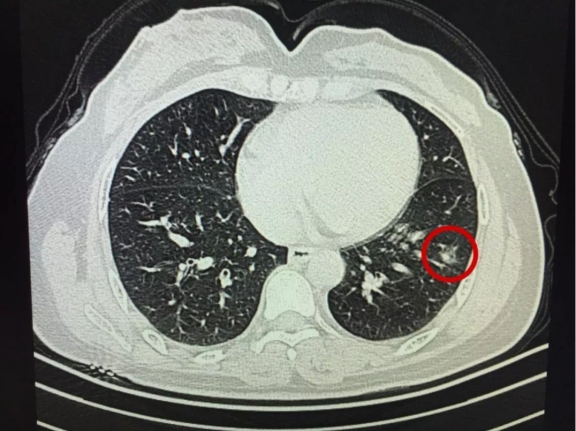

今年55岁的齐女士 , 今天到医院复查自己的肺结节情况 , 结果太让人兴奋了 , 半年的时间 , 肺结节居然变小了3mm 。 不少患者听到后 , 都开始向她取经 , 希望借鉴齐女士的方法 , 能快速的让消极缩小 。

齐女士已经退休了 , 自己其实是没有任何征兆的 , 但因为半年前出了一次车祸 , 到医院才发现有结节 。 左肺上叶磨玻璃结节0.8×0.7cm , 伴有少许炎症 , 当时医生是建议她定期复查就可以了 , 所以齐女士把车祸骨折的伤治好后 , 就出院了 。